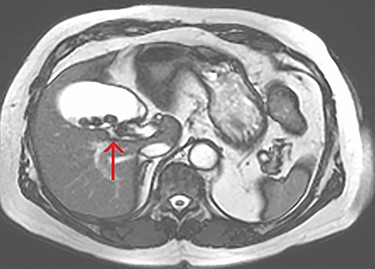

Axial view of the liver and gallbladder from a cardiac MRI showing a tubular structure entering the gallbladder at the level of the body in keeping with an accessory cystic duct (highlighted by the arrow).

The tubular structure was remote from the porta hepatis with one lumen. It was located within the distal gallbladder fossa. Inspection of the gallbladder demonstrated an opening at the same orientation and of the same calibre as this tubular structure, raising suspicion for a duplicated cystic duct. Probing the source of the bile leak confirmed a single lumen. The capacity to perform IOC was not available at the time of the operation. A review of the patient’s prior imaging was performed. Recent cardiac magnetic resonance imaging (MRI), while not dedicated magnetic resonance cholangiopancreatography (MRCP), provided adequate views of the liver, gallbladder and biliary tree to demonstrate the suspected anomaly. On these images, two structures were seen to be connecting the gallbladder to the biliary tree. One duct was observed at Hartmann’s pouch, while a second connected to the gallbladder body (Fig. 1, Fig. 2). The images confirmed suspicion of a duplicated cystic duct and the decision was made to clip the lumen. The cholecystectomy was completed and a drain placed in the gallbladder fossa.